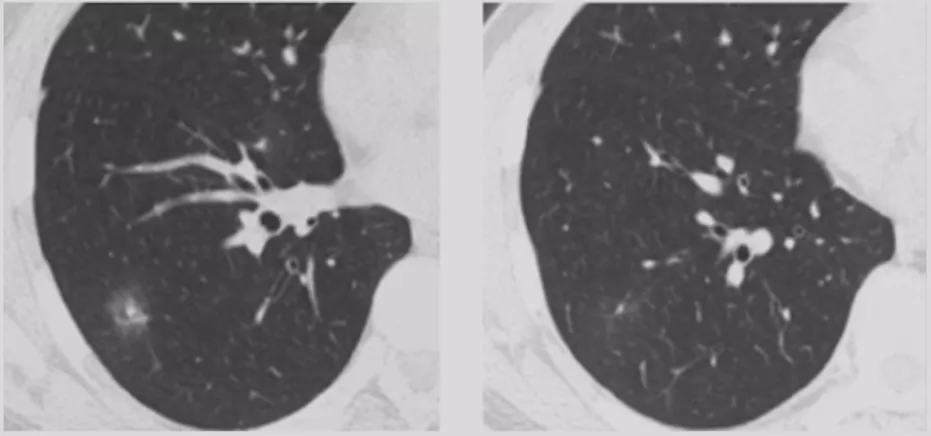

CT随访

1)病灶大小无变化、实性成分增多

这个结节大小没有太大变化,实性成分增多,这不是一个好征象,可以考虑手术。

2)病灶缩小、出现实性成分

容易被大家忽略的是结节的大小变小,但实性成分增多,值得大家重视。不要认为结节变小了就一定是良性。